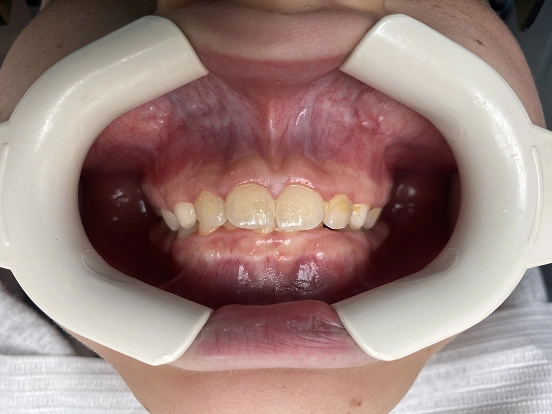

Braces MP

MP’s before and after results highlight the precision of modern braces. The treatment corrected both alignment and bite discrepancies, creating a natural-looking, even smile that enhances overall facial aesthetics and oral health.